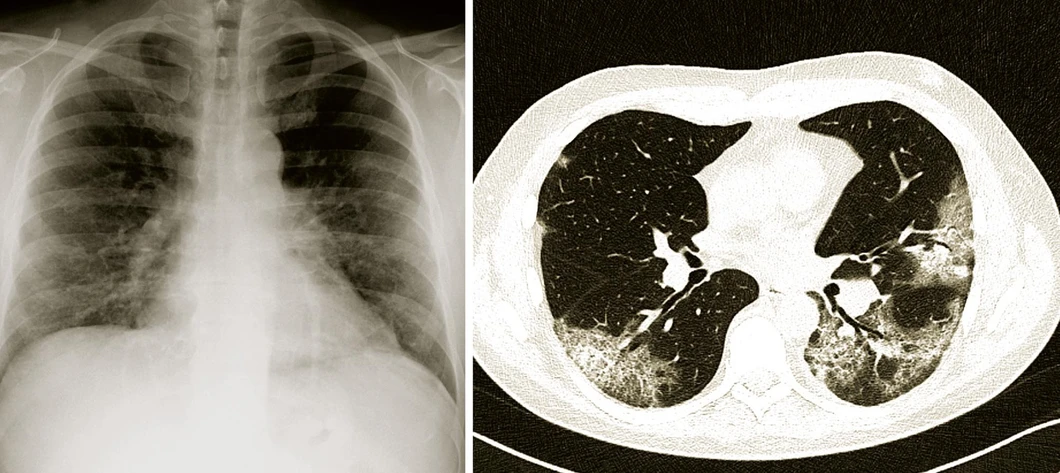

Závažnost nemoci závisí na míře plicního postižení. V akutním stavu je možné velikost plicního postižení zjistit jednak rozsahem rtg nálezu (obr. 1), jednak měřením oxygenace krve; jednoduché čidlo připojené zevně na prst nebo na ušní boltec dokáže sledovat, zda je krev v kapilárách dobře prokysličena. Při nedostatečném sycení se pacientovi podává kyslík maskou nebo nosními brýlemi. Jestliže to nestačí, mluvíme o těžkém průběhu nemoci covid-19. Pak je nutné pacienta přesunout na oddělení intenzivní péče a zahájit neinvazivní nebo invazivní ventilaci, případně ho napojit na přístroj zajišťující mimoplicní výměnu plynů (ECMO, extracorporal membrane oxygenation). Nebezpečnost plicního zánětu tím však není vyčerpána. Po odeznění akutní fáze může dlouhodobě přetrvávat zvýšená dráždivost průdušek, která vede k záchvatům dušnosti a kašle. Vzácně může nastat i nevratná vazivová přestavba plic (fibróza), omezující dýchání tím, že brání rozpínání plic při vdechu.

Vesmír/Radiodiagnostická klinika Nemocnice Na Bulovce: Snímky plic provedené různými technikami u téhož pacienta s těžkým průběhem nemoci covid-19. Na prvém obrázku (vlevo) je klasický Rtg snímek hrudníku, kde je oboustranně v dolních polích plicních lehce snížená transparence a zvýšená bronchovaskulární kresba – poměrně mírný rozsah tohoto nálezu dostatečně nekoresponduje se závažností respirační insuficience. Druhý snímek (vpravo) získaný počítačovou tomografií (CT) ukazuje neostře ohraničené okrsky tzv. „opacit mléčného skla“ a „crazy paving“, které jsou typické pro plicní postižení při nemoci covid-19. Tento nález lépe osvětluje těžký průběh onemocnění.Vesmír/Radiodiagnostická klinika Nemocnice Na Bulovce: Snímky plic provedené různými technikami u téhož pacienta s těžkým průběhem nemoci covid-19. Na prvém obrázku (vlevo) je klasický Rtg snímek hrudníku, kde je oboustranně v dolních polích plicních lehce snížená transparence a zvýšená bronchovaskulární kresba – poměrně mírný rozsah tohoto nálezu dostatečně nekoresponduje se závažností respirační insuficience. Druhý snímek (vpravo) získaný počítačovou tomografií (CT) ukazuje neostře ohraničené okrsky tzv. „opacit mléčného skla“ a „crazy paving“, které jsou typické pro plicní postižení při nemoci covid-19. Tento nález lépe osvětluje těžký průběh onemocnění.